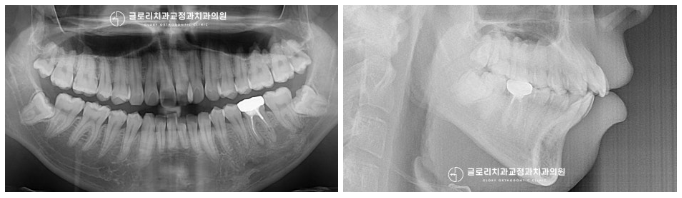

가져온 사진을 보면

위와 같은 치열 문제들을 확인할 수 있으며,

발치 예정인 어금니도 관찰됩니다.

예시 사진을 보니,

임플란트 식립이 필요할 것으로 판단됩니다.

신내동 교정치과 에서 준비한 측면 사진을 비교해 보니

그 차이가 더 크게 느껴지는데요.